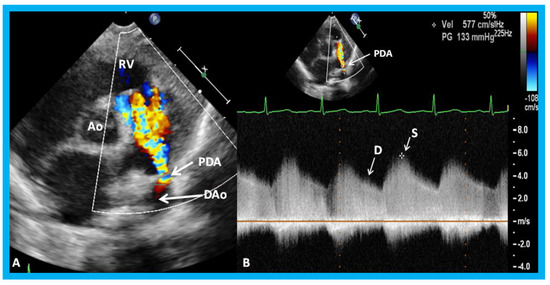

16. The Role of Echocardiographic Investigation in the Evaluation of Patent Ductus Arteriosus in the Preterm Babies

The PDA produces left-to-right shunt, largely in proportion to the minimal ductal diameter. In premature babies, such shunts produce pulmonary and cardiac compromise. Although the clinical features, chest x-ray, and serum brain natriuretic peptide (BNP) levels are helpful in identifying a PDA, hemodynamically significant PDAs are best detected and quantified with the help of echo-Doppler studies [33,34,35]. The echocardiographic finding of PDA in the premature were reviewed in detail elsewhere [33,34,35] and may be summarized as follows. The left atrium (LA), LA:aortic root (Ao) ratio (<1.4:1), and the left ventricle (LV) are expected to be normal in size in small PDAs, and the systolic function of the LV is preserved. In large PDAs, dilatation of the LA and LV and increase in LA:Ao ratio is (>1.6:1) are seen. At first, the function of the LV is normal or hyperdynamic, and with time, the function of the LV may get worse with consequent elevation in LV end-diastolic and LA pressures. These hemodynamic abnormalities may cause further worsening of the respiratory function. In babies with moderate PDAs, the parameters in are in middle with moderately dilated LA (LA:Ao ratio of 1.4 to 1.6) and LV. In the majority of the babies, the systolic function of the LV remains normal.

In small PDAs, the Minimal ductal diameter (MDD) is small and there is a high Doppler velocity across the PDA (Figure 32), while in large PDAs, the MDD is large and there is a low Doppler velocity across them (Figure 33). In moderately sized PDAs, these parameters are somewhere in between. The pulmonary artery (PA) pressures are usually normal in small PDAs, whereas the PA pressures are probably elevated in large PDAs. While the above statements are mostly accurate, the pressures in the PA also depend upon the magnitude of pulmonary parenchyma disease. Furthermore, in very low birth weight infants, the pressures in the PA may not be increased corresponding to the pulmonary parenchyma disease because of underdeveloped pulmonary vasculature in the premature.

Lastly, in small PDAs, normal diastolic anterograde flow is seen descending aorta (Figure 34), while in large PDAs, either no normal anterograde diastolic flow or retrograde diastolic flow (Figure 35) is seen in the descending aorta. Most of the medium-sized PDAs have normal diastolic anterograde flow in the descending aorta.

Clinicians caring for premature babies may be able to determine the size of the PDA by the evaluation of the diameter of the LA, LA:Ao ratio, the LV dimension, estimated pressures in the pulmonary artery, MDD, magnitude of Doppler flow velocity across the PDA, and flow patterns in the descending aorta (Table 2). A baby with medium-to-large PDA in association with respiratory compromise may be characterized as having hemodynamically significant PDA [33,34,35].